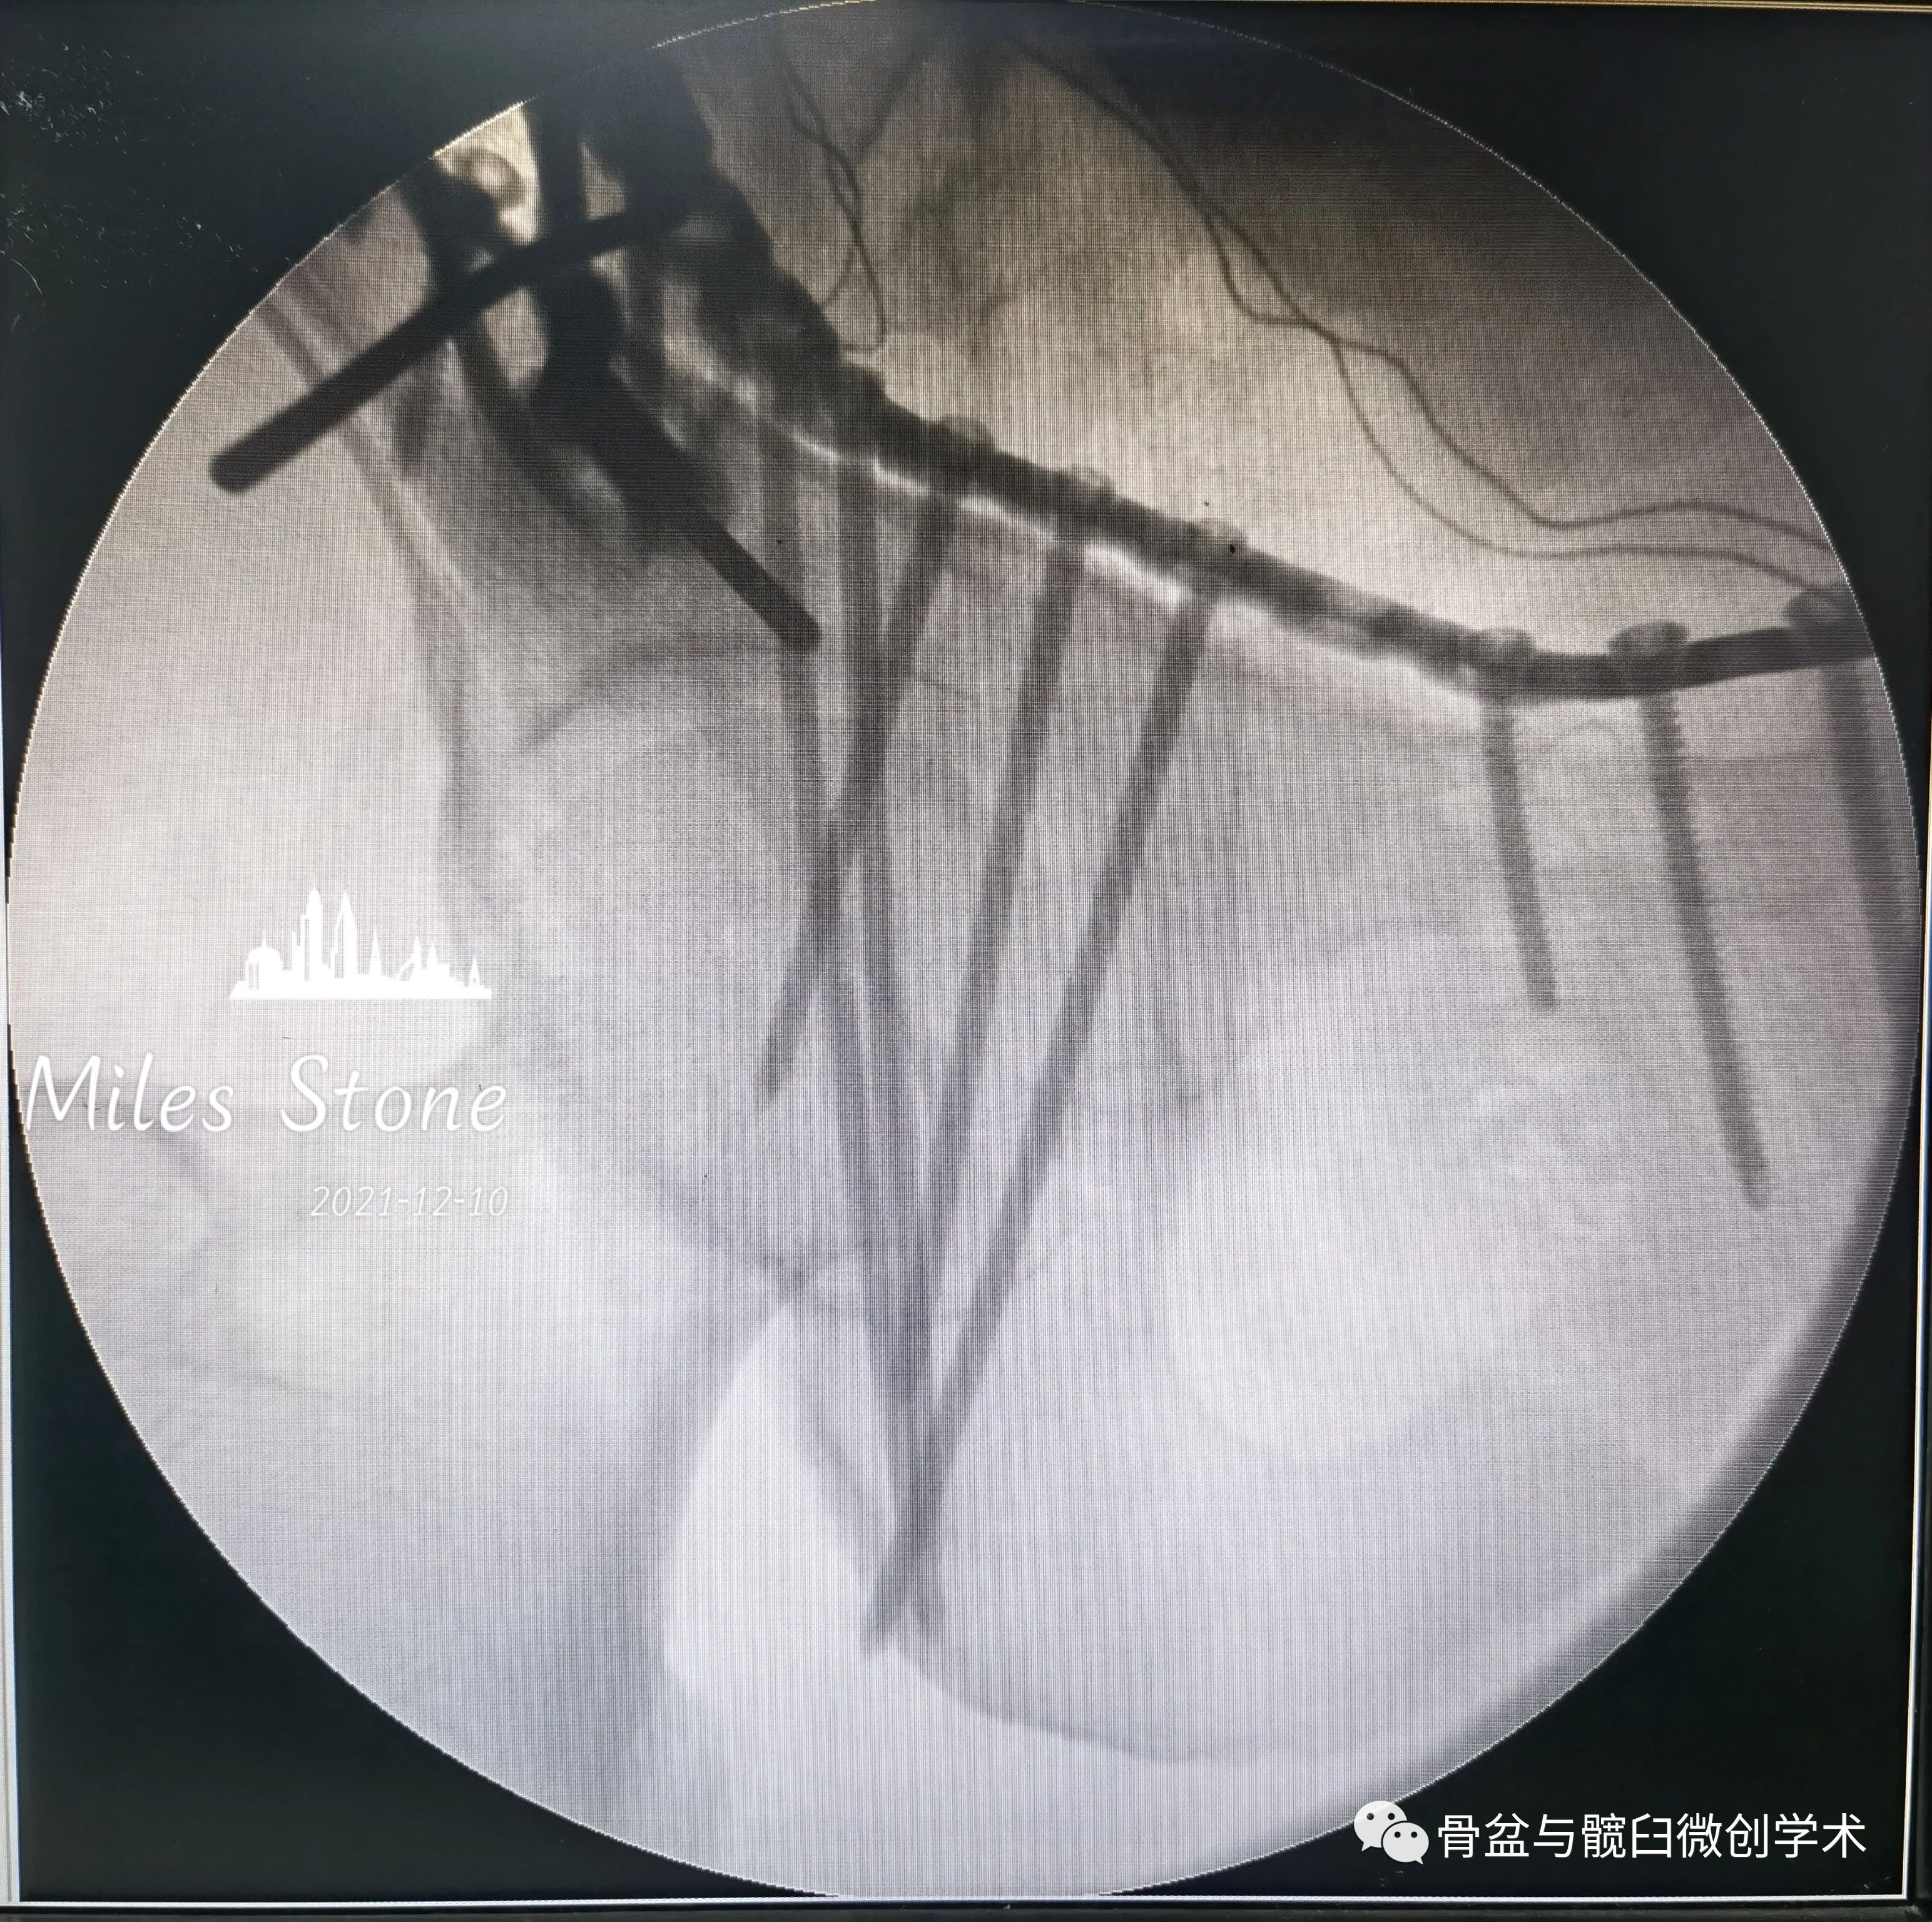

用2.5mm直径克氏针代替钻头,使钻孔操作更顺畅。

Taking the place of the drill, a 2.5mm in diameter K-wire will make the drilling much more uneventful.

在2窗内钻孔,要在克氏针上套上一截儿输液管,以防绞缠神经血管。

When you are drilling in the second window,

it is safe to put a length of infusion tube over the K-wire,which will prevent neorovascular structures from being enwound.